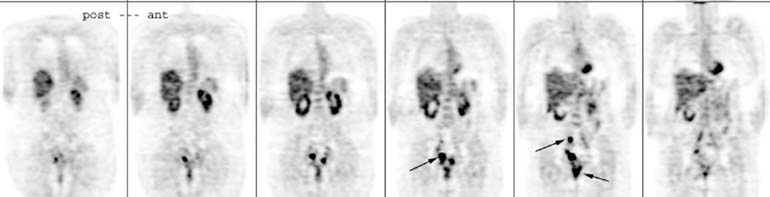

Fig. 2. 2-[18F]-Fluoro-2-deoxy-d-glucose–positron emission tomography (FDG-PET) scan, selected coronal images. Normal uptake in the liver, heart, kidneys, and bone marrow. Patient with recurrent ovarian cancer with multiple lung nodules, considered for resection of lung metastasis. PET scan shows multiple hypermetabolic foci, consistent with widespread metastases in the lungs, mediastinum and around the liver (arrows). Surgery was cancelled; the patient died 1 month later.